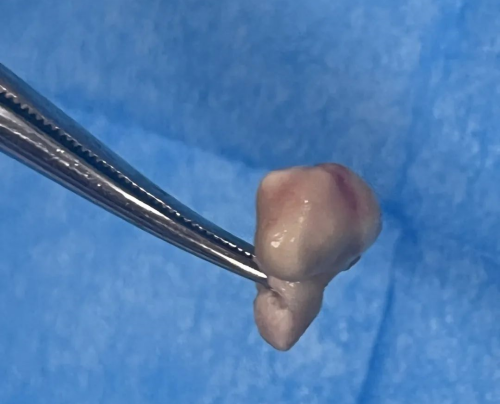

8月20日,手术顺利进行。术中,杨继承不仅成功摘除了李阳玲心脏的那颗2厘米脓球状赘生物,还发现了因赘生物侵蚀而导致的三尖瓣前瓣2厘米缺损及三尖瓣关闭不全的问题。为了修复这一损伤,杨主任巧妙地取用了患者自身的心包片作为“补丁”,并使用细如发丝的缝合线进行了精细的修补。手术取得了圆满成功,李阳玲术后恢复迅速,当天即恢复意识,第二天便脱离了呼吸机,第三天便转入心胸外科继续治疗,现已康复出院。